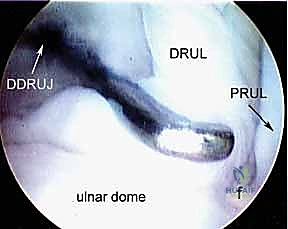

Dorsal Distal Radioulnar Joint (DRUJ) Portals

These portals offer direct access to the DRUJ for assessing its articular cartilage and ligaments.

1. The Dorsal Radioulnar Joint Portal (Proximal and Distal)

- Location: Lies between the ECU and the EDM tendons. There can be a proximal (PDRUJ) and a distal (DDRUJ) portal.

- Anatomy: The interval between the fifth (EDM) and sixth (ECU) extensor compartments.

- Neurovascular Risks: Transverse branches of the dorsal cutaneous branch of the ulnar nerve are the only sensory nerves in proximity, typically at a mean of 17.5 mm distally (range 10–20 mm) from the portal. Careful dissection is still advised.

- Function: Used in concert with the volar distal radioulnar portal to fully assess the articular cartilage of the ulnar head and sigmoid notch, and for instrumentation within the DRUJ.